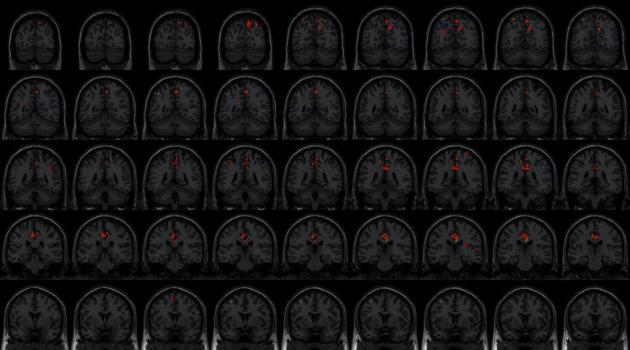

RESULTS

The difference in the NIHSS score between the two groups of patients before and after treatment was statistically significant (tNIHSS = 2.225; PNIHSS = 0.038), indicating that TG had a better effect. Centered to the seed region of the left supplementary motor area (SMA) (-5.32, 4.85, 61.38), FC increased at the left middle cerebellar peduncle, left cerebellum posterior lobe (uvula and declive), vermis, fusiform gyrus, lingual gyrus, inferior occipital gyrus, calcarine, cuneus, precuneus, BA7, BA18 and BA19, etc. Centered to the seed region of the left parahippocampal gyrus (PG) (-21.17, -15.95, -20.70), FC increased at the left precuneus, inside-paracingulate, inferior parietal gyrus, paracentral lobule, BA5, BA6, BA7, and BA40, right median cingulate, precuneus, BA19, BA23, and BA31, etc.

CONCLUSIONS

It is indicated that ISSA can regulate the brain functional connection in patients with middle cerebral artery acute infarction in the dominant hemisphere and specifically strengthen the connections between visual, cognitive, motor control, and planning-related brain regions, which may be related to the recovery of movement in the mechanism. This trial is registered with ChiCTR-IOR-15007672.

结果

两组患者治疗前后NIHSS评分差异有统计学意义(tNIHSS = 2.225;PNIHSS = 0.038),表明治疗组效果更佳。以左侧辅助运动区(SMA)的种子区(-5.32, 4.85, 61.38)为中心,左侧小脑中脚、左侧小脑后叶(蚓垂和蚓部)、蚓部、梭状回、舌回、枕下回、距状裂、楔叶、楔前叶、BA7、BA18和BA19等区域的功能连接增加。以左侧海马旁回(PG)的种子区(-21.17, -15.95, -20.70)为中心,左侧楔前叶、内侧扣带回、顶下小叶、中央旁小叶、BA5、BA6、BA7和BA40、右侧正中扣带回、楔前叶、BA19、BA23和BA31等区域的功能连接增加。

结论

表明靳三针疗法可调节优势半球大脑中动脉急性梗死患者的脑功能连接,特异性加强视觉、认知、运动控制及计划相关脑区之间的连接,这可能在机制上与运动功能恢复有关。本试验已在中国临床试验注册中心注册,注册号为ChiCTR-IOR-15007672。